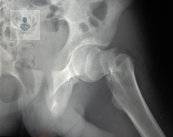

Osteoporosis: Una enfermedad silenciosa que debilita los huesos

La Osteoporosis es una condición que afecta la salud ósea y puede pasar desapercibida durante años. Su importancia radica en que aumenta de forma significativa el riesgo de Fracturas, lo que puede modificar de manera importante la calidad de vida.